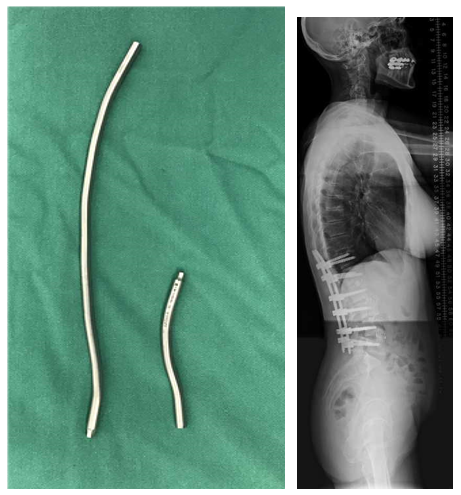

(1)横突钩和移行棒

图28-29 据文献报道,对于UIV应用横突钩和移行棒可以一定程度避免PJK/PJF的发生

T10骨盆固定,出现交界性后凸

行翻修手术:T9/10SP截骨,延长到T4固定,预防性双侧肋骨固定(VEPTR)

图32-33 肋骨固定